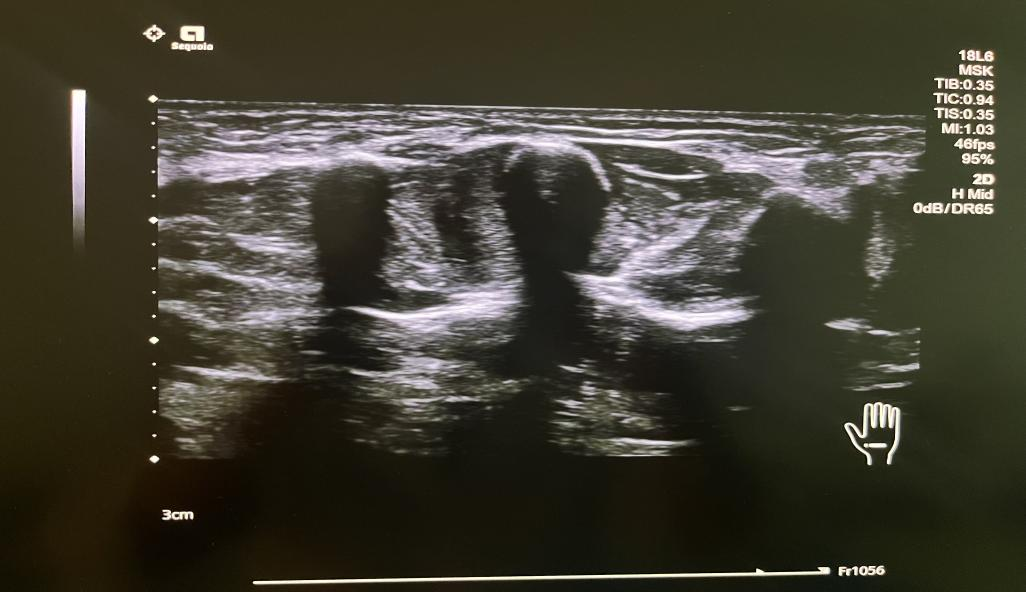

18L6超高频线阵探头

超高频线阵探头下的肌骨超声图像

新设备具备相关临床应用技术,满足于心脏、腹部、胃肠、妇科、产科、浅表器官、肌骨关节、外周血管、颅脑等超声检查。